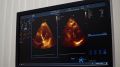

В рамках недели осведомлённости о заболеваниях сердца мы поговорили с врачом о том, кто сегодня в группе риска, какие симптомы нельзя игнорировать, какие обследования стоит проходить даже при хорошем самочувствии и что действительно помогает сохранить здоровье сердца.